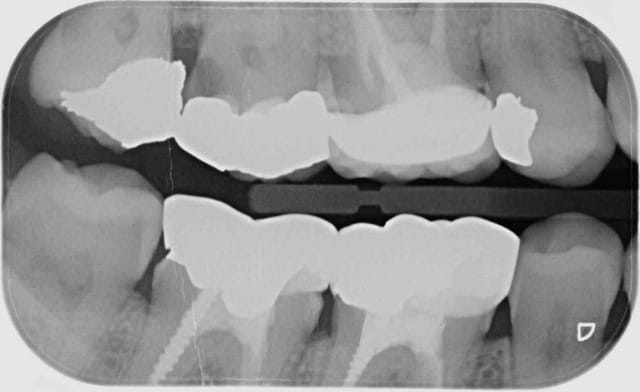

Ici on peut voir 4 secteurs distincts de 3 dents contigues en rétro-coronaires aussi pourquoi pas.

Toujours ce quelque soit le nombre de clichés hein ?

18, 17, 16 - 16, 15, 14

48, 47, 46- 46, 45, 44

Je mets la définition de distinct pour que ca soit clair. Ces secteurs ne se confondent pas. -)

C'est pratique ces libellés plus on creuse et moins c'est clair. -)

La notion de centre est primordiale. Une seule radio, un seul centre un seul secteur.

Sauf pour les rétro coronaires ou tu peux centrer sur 2 secteurs.

Ici tu ne peux coter que 2 secteurs de 1 a 3 dents contigues dents contigues. radio centrée sur 46 et 16 donc 2 secteurs distincts.

47,46,45 et 17,16, 15.